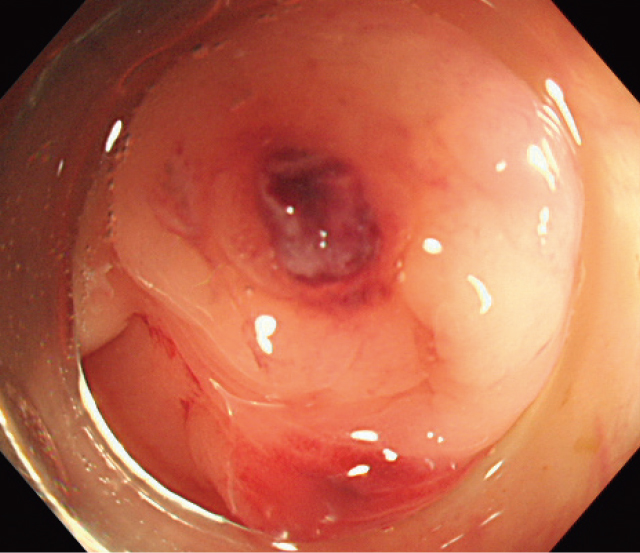

Active Bleeding(AB).

憩室から活動性出血を認める.